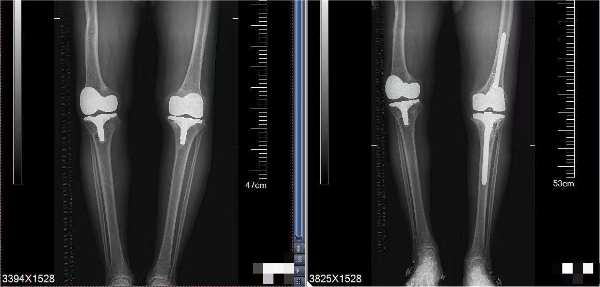

患者在省内辗转多家医院,得知王伟教授在洛阳市中心医院骨科工作,相信困难会被解决。王伟教授率领骨科关节团队,仔细分析病情,观测炎症指标,并邀请西交大二附院骨科全国骨科顶级专家,中华医学会骨科分会候任主任委员王坤正教授团队远程会诊,做出最终研判:患者并非关节感染,是由于左下肢长了4厘米,长期关节不平衡,造成患者左膝关节机械性松动。如何翻修手术,刘营杰主任提前精细测量患者下肢畸形角度、下肢长度,做出术前规划,提前定制矫形鞋,纠正下肢不等长。王伟教授、王伟民主任制定术前预案,一期做了左膝关节翻修手术,术后证实,患者诊断完全符合术前判断。经过两周的精心护理,患者顺利出院。术后1个月复查,患者已完全脱离了拐杖,恢复了正常生活。患者从10万余元的预算到最终花费5万余元,为患者减轻了经济负担,精准的诊断为患者缩短了治疗时间。